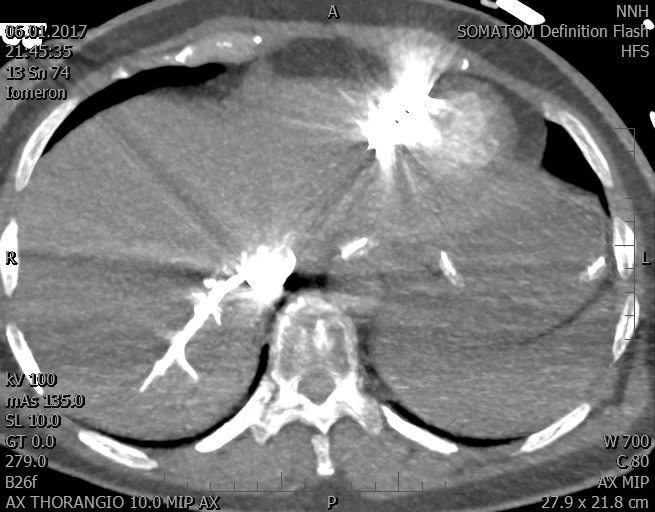

Video 2 - Echokardiograficky byla zjištěna těžká dysfunkce dilatační levé komory s nezvětšenou pravou komorou.Pro nejasnou příčinu zástavy jsme provedli i vyšetření výpočetní tomografií (CT), které vyloučilo plicní embolizaci (série 1 - soubory na konci článku). V den přijetí při přetrvávající oběhové nestabilitě byla nemocná opakovaně defibrilována pro fibrilaci komor se stabilizací rytmu po podání amiodaronu a mesocainu. Dle hemodynamických měření se jednalo o těžký kombinovaný šok. Vstupní laboratorní vyšetření bylo bez větších pozoruhodností. Posléze jsme doplnili anamnézu od příbuzných a zjistili, že pacientka užila do dvou hodin před srdeční zástavou první tabletu amoxicilinu na lehký respirační infekt. Při nevýtěžnosti vstupních vyšetření a nových anamnestických informacích jsme doplnili 14 hodin po kolapsu vyšetření koncentrace tryptázy v séru, která byla extrémně zvýšena (tabulka 2), což nás vedlo k podezření na anafylaxi.